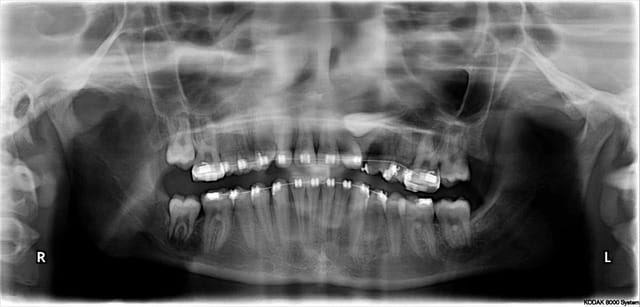

Je suis en plein traitement ortho pour une legere classe 3 canine gauche et une legere rotation de 22.

le cas montré par D57 est intéressant, magistralement exécuté, mais n'est pas forcément un cas "d'école" à suivre, bien au contraire puisque ici le choix stratégique normal aurait été de tracter la 25 et non de l'extraire...d'autant, encore une fois, que la mise en place ne posait aucune difficulté majeure...

donc oui, bravo pour la chir...et dommage pour cette 25...

d'autant plus dommage qu'avec 3mm d'ancrage, c'est "chaud" pour une mise en esthétique immédiate, perso je n'aurais pas osé tenter...

Donc j'avais bien compris, tu as extrait 44 pour extraire 45 et ça te semble normal parce que son extraction aurait été risquée autrement. Difficile pour moi de critiquer ce choix sans avoir d'autres éléments de diagnostic que la pano. Mais je t'expose ma solution: extraire la 44 sans toucher la 45 malgré l'accés linguale et la difficulté opératoire. Sinon ne pas toucher et surveiller, voir meme espérer une éruption linguale.

Tu disais précédemment que le meilleur implant c'était la dent, en fait le meilleur implant, c'est pas d'implant.